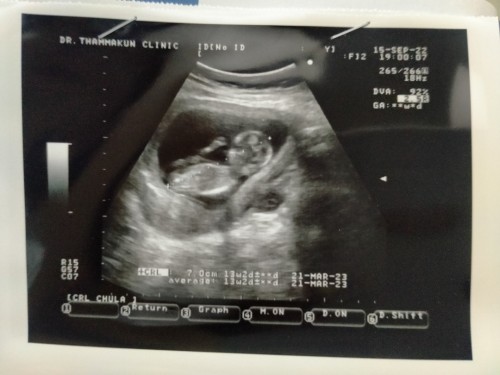

13w 1d น้องยาว 6.7 น้องปกติไมคะ ไปซาวด์มาแล้ววันนี้คะ

บ้านนี้ไปเมื่อวานน้อง7cm. หมอบอกตัวโตขึ้นเยอะเลยค่ะ